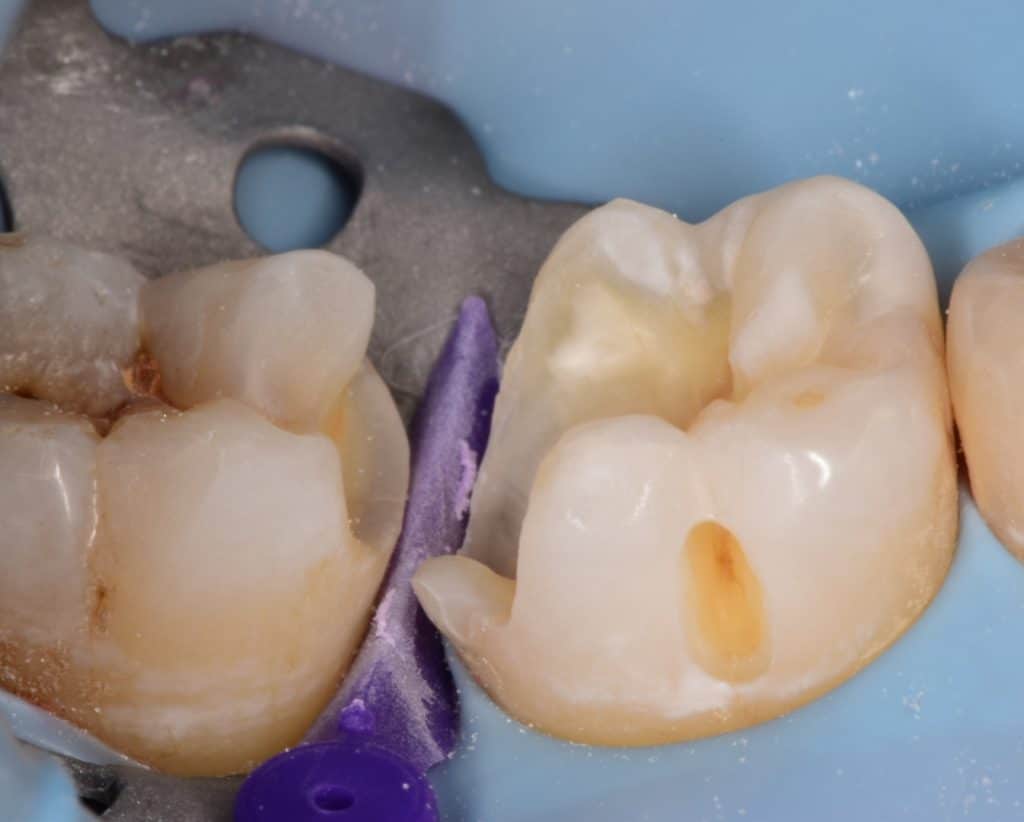

Saddle metal band placed in it's place, the cavity sandblasted and etched again and adhesive application followed

Immediate result

Immediate result before final finishing and polishing

Immediate result after finishing and polishing